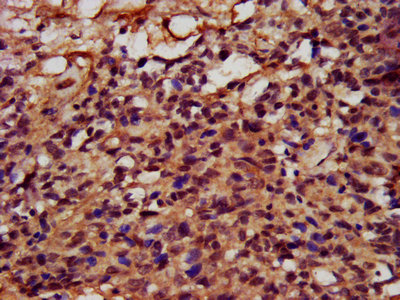

IHC image of PACO38678 diluted at 1:400 and staining in paraffin-embedded human testis tissue performed on a Leica BondTM system. After dewaxing and hydration, antigen retrieval was mediated by high pressure in a citrate buffer (pH 6.0). Section was blocked with 10% normal goat serum 30min at RT. Then primary antibody (1% BSA) was incubated at 4°C overnight. The primary is detected by a biotinylated secondary antibody and visualized using an HRP conjugated SP system.

IHC image of PACO38678 diluted at 1:400 and staining in paraffin-embedded human ovarian cancer performed on a Leica BondTM system. After dewaxing and hydration, antigen retrieval was mediated by high pressure in a citrate buffer (pH 6.0). Section was blocked with 10% normal goat serum 30min at RT. Then primary antibody (1% BSA) was incubated at 4°C overnight. The primary is detected by a biotinylated secondary antibody and visualized using an HRP conjugated SP system.